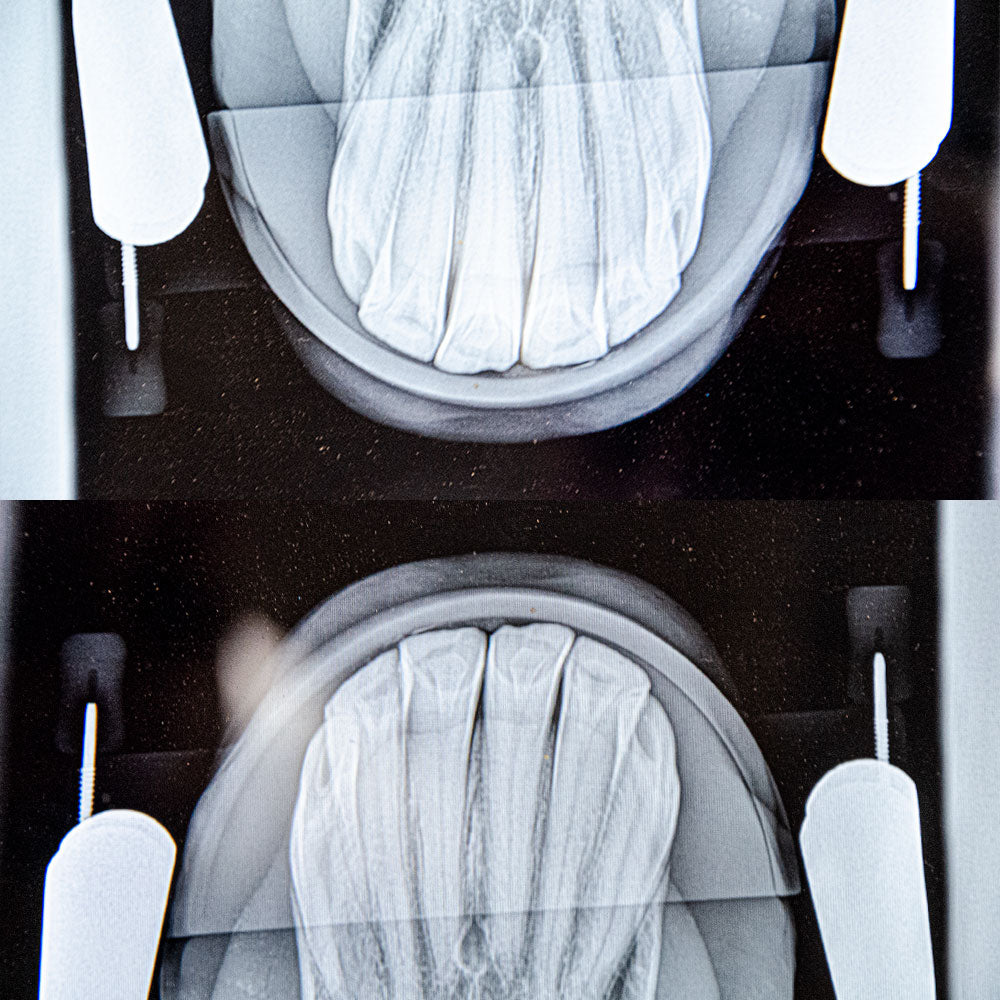

The radiolucent X-ray plates are designed for performing intraoral radiographic projections of the incisors and lower canines, ensuring the digital X-ray sensor is positioned safely within the mouth.

Crafted from radiolucent material, these plates allow the X-ray beam to pass through without compromising the quality of the radiographic image. This feature enables the effective execution of the intraoral bisecting angle technique, resulting in high-quality images of the reserve crown and apical region of the incisors and canines.

The plates feature a lateral locking system for universal compatibility with mouth openers (speculum), ensuring stability and ease of use during procedures.